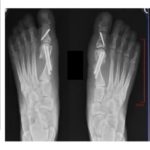

MIS Bunion Correction

Courtesy: Noman Siddiqui, Fellowship Director, Rubin Institute of Advanced Orthopaedics, Baltimore, Maryland, USA

Courtesy: Dr Paul Kim MD, MIS Foot and Ankle Surgeon, California Orthopaedics and Spine, California, USA